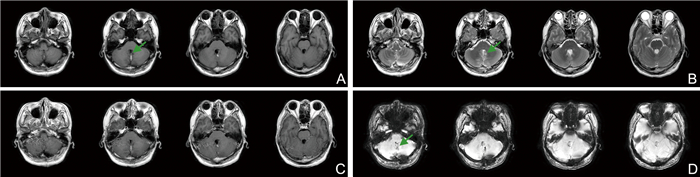

The expression of serum miR-760-3p and miR-182-5p in patients with acute ischemic stroke and their relationship with prognosis

DUAN Kaiqiang, WU Yanfeng, XUE Jiahai, WANG Wei, LI Chunling, LI Juan

2025, 23(10): 1701-1705. doi: 10.16766/j.cnki.issn.1674-4152.004209

37 2

Abstract:

Objective  By detecting the expression of serum miR-760-3p and miR-182-5p in patients with acute ischemic stroke (AIS), aimed to further explore their relationship with the patient ' s condition and prognosis.  Methods  From February 2022 to February 2024, 179 patients with AIS admitted to Zhangjiakou First Hospital were selected as the observation group, and divided into a mild group of 59 cases, a moderate group of 75 cases, and a severe group of 45 cases, and 179 healthy individuals who underwent physical examinations at our hospital were regarded as the control group. According to the patient ' s prognosis, they were divided into a good prognosis group 132 cases and a poor prognosis group 47 cases. The correlation between serum miR-760-3p and miR-182-5p expression levels and NIHSS score, the prognostic factors of patients with AIS, and the predictive value of serum miR-760-3p and miR-182-5p for the prognosis of patients with AIS were analyzed.  Results  The expression levels of miR-760-3p and miR-182-5p in the observation group and poor prognosis group were lower than those in the control group and good prognosis group, respectively (P < 0.05). As the severity of the disease deepens, the expression levels of miR-760-3p and miR-182-5p in the patient ' s serum decreased sequentially (P < 0.05). The expression levels of serum miR-760-3p and miR-182-5p were negatively correlated with NIHSS scores (rs=-0.578, -0.618, P < 0.001). The age, smoking history, hypertension history, and serum miR-760-3p and miR-182-5p were influencing factors for poor prognosis in patients with AIS (P < 0.05). ROC curve results showed that the AUC of their combination in predicting the prognosis of AIS patients was higher than that of miR-760-3p and miR-182-5p alone (P < 0.05).  Conclusion  The downregulation of miR-760-3p and miR-182-5p expression in the serum of AIS patients was closely related to prognosis.